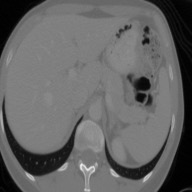

This work presents a novel framework CISFA (Contrastive Image synthesis and Self-supervised Feature Adaptation)that builds on image domain translation and unsupervised feature adaptation for cross-modality biomedical image segmentation. Different from existing works, we use a one-sided generative model and add a weighted patch-wise contrastive loss between sampled patches of the input image and the corresponding synthetic image, which serves as shape constraints. Moreover, we notice that the generated images and input images share similar structural information but are in different modalities. As such, we enforce contrastive losses on the generated images and the input images to train the encoder of a segmentation model to minimize the discrepancy between paired images in the learned embedding space. Compared with existing works that rely on adversarial learning for feature adaptation, such a method enables the encoder to learn domain-independent features in a more explicit way. We extensively evaluate our methods on segmentation tasks containing CT and MRI images for abdominal cavities and whole hearts. Experimental results show that the proposed framework not only outputs synthetic images with less distortion of organ shapes, but also outperforms state-of-the-art domain adaptation methods by a large margin.